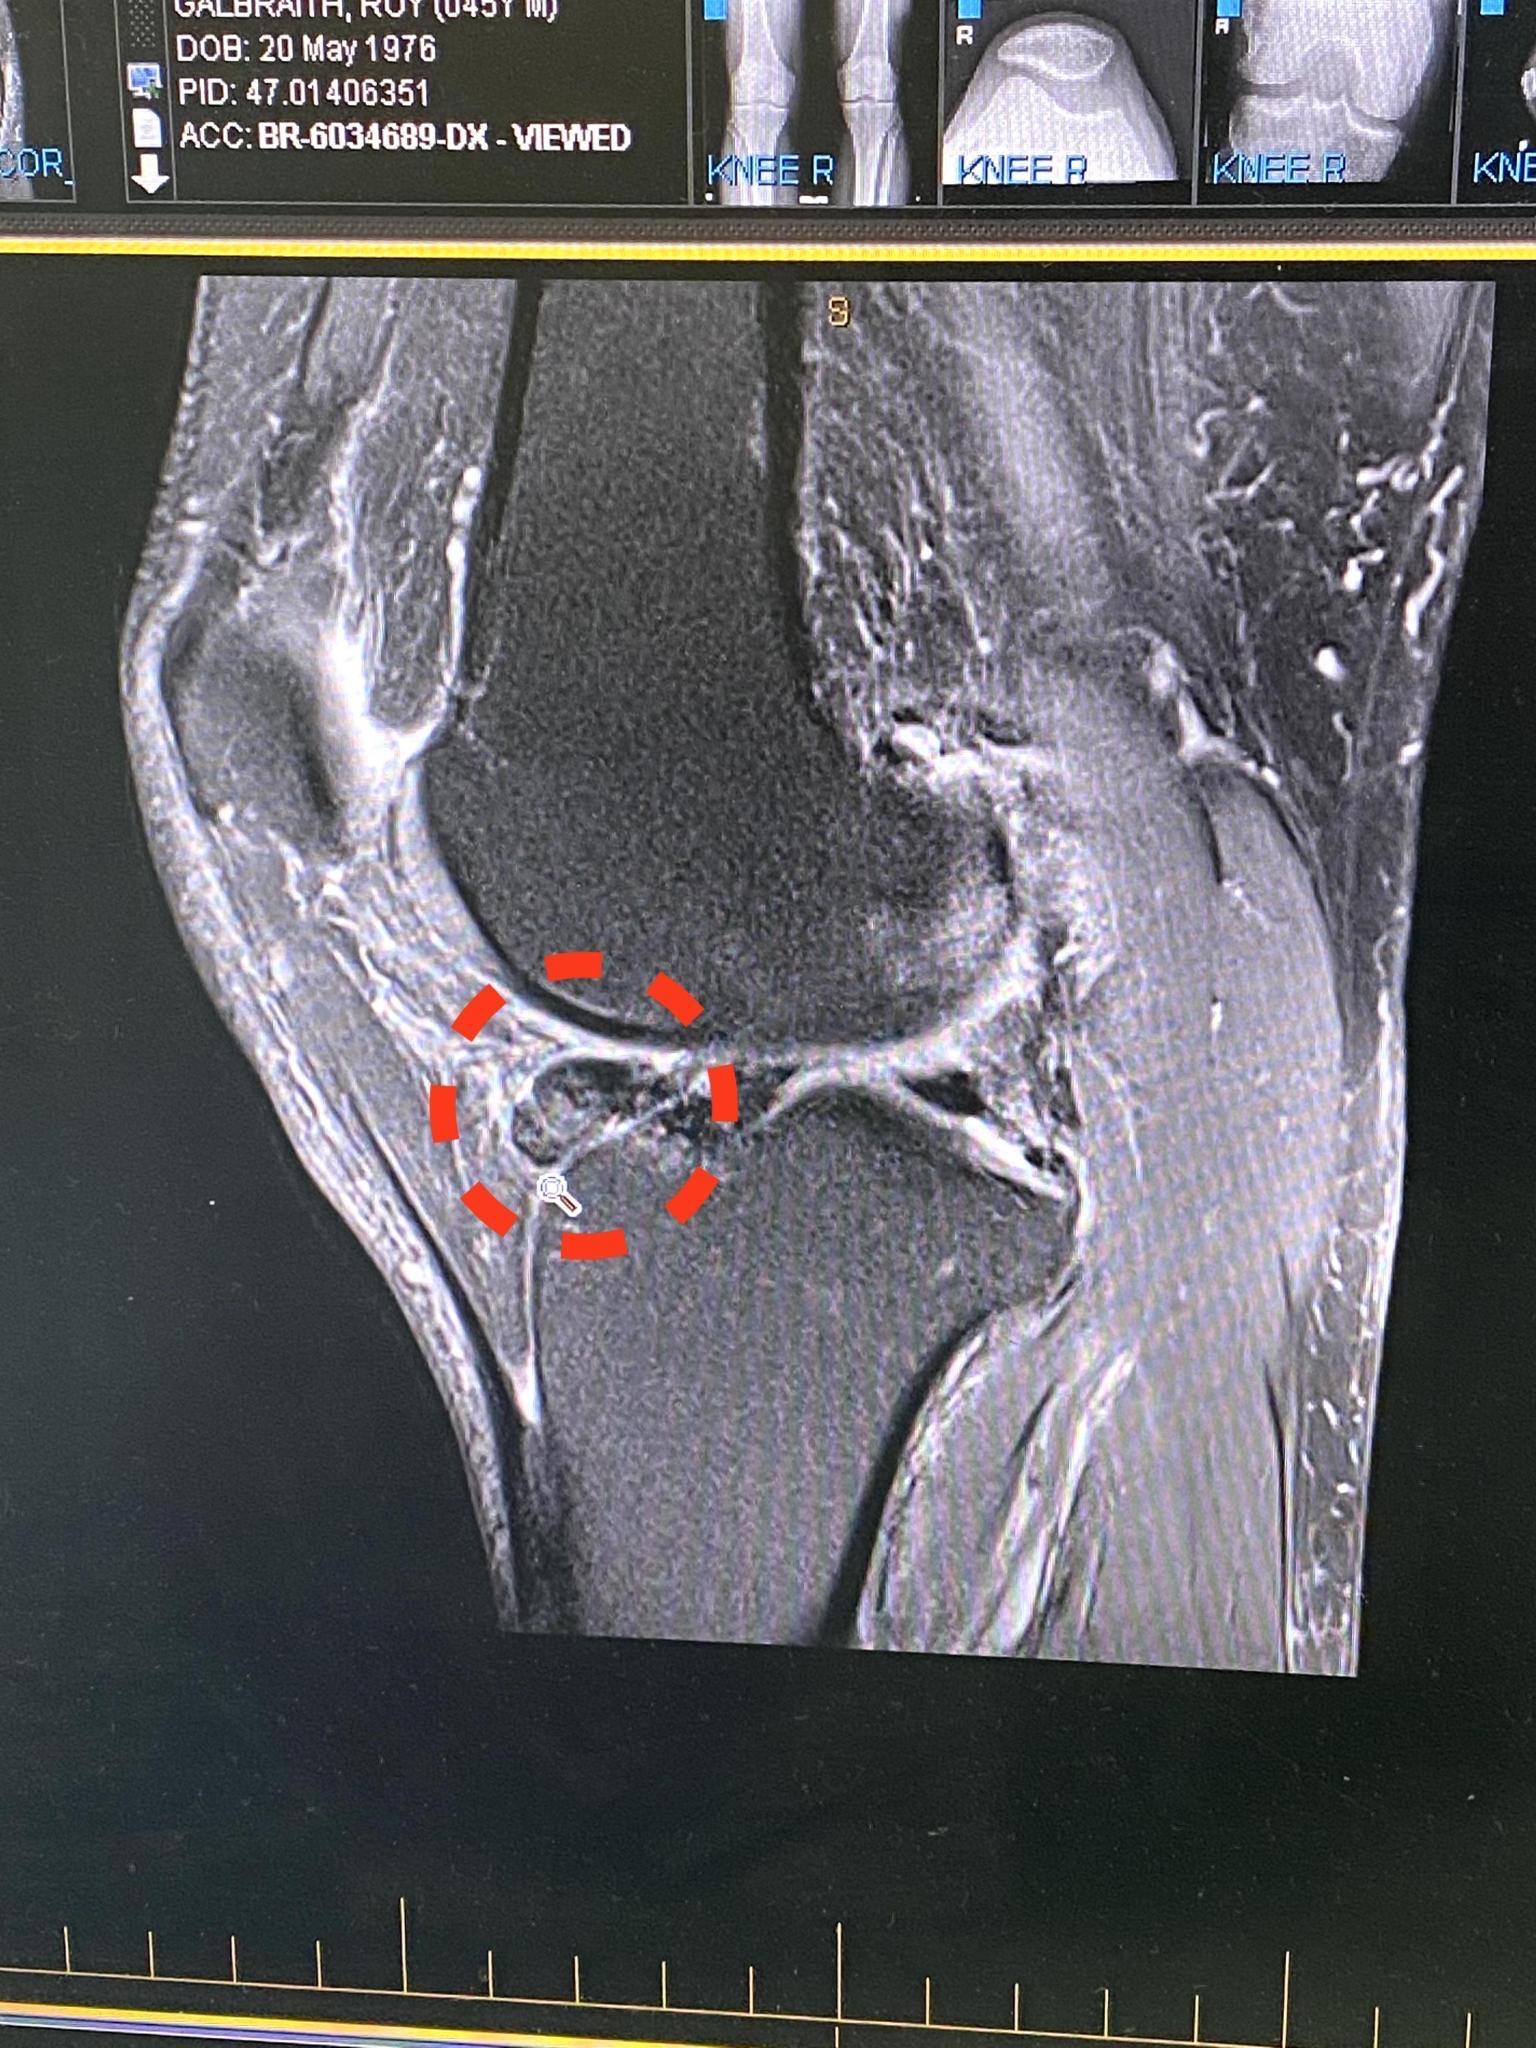

So many questions and so few answers, but when you hear the word Tumour your mind plays tricks and it is then very hard to completely take everything else in terms of what is being said, the next keywords were – “I will be referring you to the Tumour Clinic at Flinders Cancer Clinic” for further care/treatment. Hey, this is not my first rodeo, can we have a quick chat about options, I was not looking for a clinical plan in terms of treatment. I wanted to understand deeper what it was and from an orthopedic viewpoint only how this would be tackled. Surgically remove the tumour on the inside of the knee, arthroscopically repair the tear but the concern was the tumour is basically right in the middle of the knee joint between the Femur and the Tibia, there was further chat about whether the tumour is attached to the bone or not.

Today (04/04) was the answer day, let’s not beat around the bush… the diagnosis was better than we had planned for 100%, it is a rare disorder called Pigmented Villonodular Synovitis (PVNS), it is thought to affect 2 people in every 1 million. While the initial diagnosis was a huge win and relief, this disorder comes with its own sets of challenges, the particular tumour name is Giant Cell Tumour.

GCT – is a rare, aggressive non-cancerous tumour.

Back to my story, we have been advised that while I have 2 well-formed tumours (as below), there are approx 2-3 pebbles within and around the joint to consider as well, these must be removed. If untreated the risk is the tumour keeps growing, but will bleed, this will then have further impacts and will attack the bone and cartilage causing more damage.